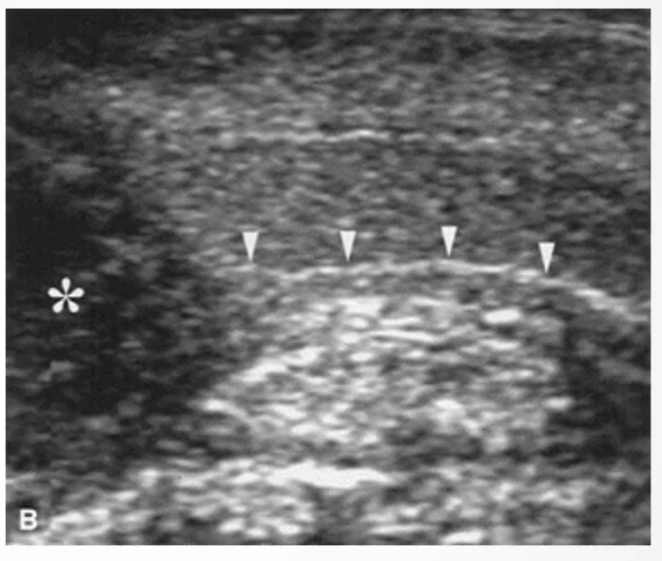

Longitudinal view demonstrating hypoechoic SCC () invading through the echogenic line of the tunica albuginea (arrowheads)*